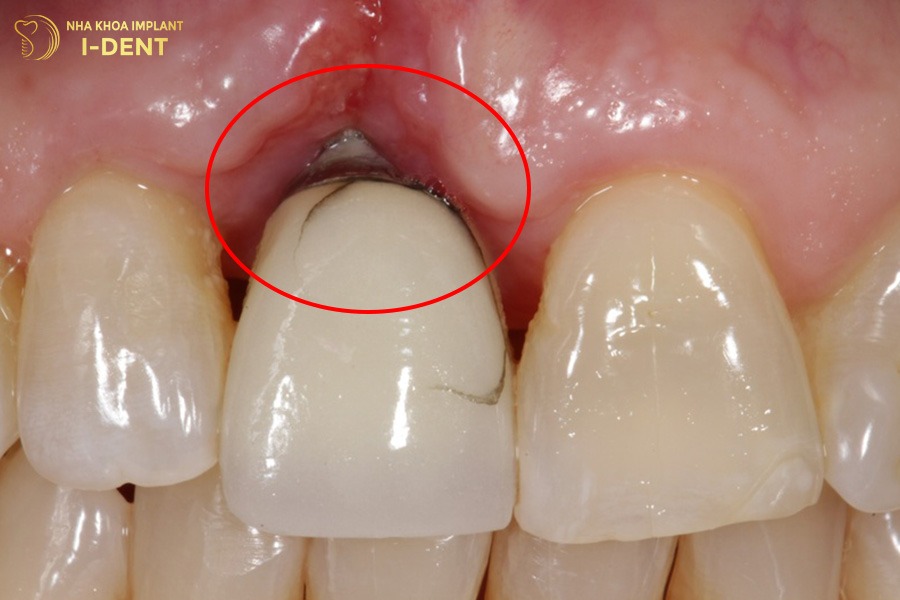

Nếu vật liệu cấu tạo nên trụ implant không đạt chất lượng thì nguy cơ hôi miệng là rất cao. Trường hợp bệnh nhân bị dị ứng với thành phần của răng implant, tình trạng mùi hôi còn trở nên nặng nề hơn. Đặc biệt, những loại sứ kim loại hoặc titan kém chất lượng có lẫn tạp chất như chì, kẽm,… dễ bị oxy hóa trong khoang miệng dưới tác động của axit từ nước bọt, thức ăn và đồ uống. Lâu dần, hiện tượng này có thể dẫn đến viền nướu bị thâm đen, viêm nhiễm và tạo môi trường thuận lợi cho vi khuẩn phát triển.

Trụ implant kém chất lượng dễ gây biến chứng và hôi miệng.

Nếu bệnh nhân lựa chọn nha khoa kém uy tín, gặp phải bác sĩ tay nghề yếu thì các mô mềm trong khoang miệng rất dễ bị tổn thương.Phục hình sai trên implant chẳng hạn như răng sứ không khít sát, không bám chắc với mô lợi và mô nha chu sẽ tạo ra khe hở trong khoang miệng. Đây là điều kiện lý tưởng cho vi khuẩn xâm nhập. Khi vi khuẩn phát triển chúng phân hủy mô răng và nướu, sản sinh ra các hợp chất lưu huỳnh dễ bay hơi có mùi hôi khiến hơi thở của bệnh nhân ngày càng nặng mùi.